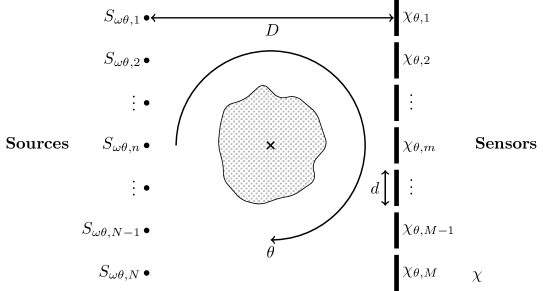

Our goal is to reconstruct the acoustic absorption profile of a region located between an array of ultrasound sources and an array of sensors through transmission UST, using the parallel array geometry shown in Figure 1. This source–sensor geometry can be compared to previous work in both UST as well as traditional x-ray computed tomography. The parallel array consists of a linear array of N𝑁N point sources Sωθ,n,n{1,,N}subscript𝑆𝜔𝜃𝑛𝑛1𝑁S_{\omega\theta,n},n\in\{1,\ldots,N\} opposing a linear array of M𝑀M sensors taken to be simply the integral over a finite support function χθ,mχ,m{1,,M}formulae-sequencesubscript𝜒𝜃𝑚𝜒𝑚1𝑀\chi_{\theta,m}\subset\chi,m\in\{1,\ldots,M\} of width d𝑑d. We consider an infinite Euclidean domain χ=2𝜒superscript2\chi=\mathbb{R}^{2}, so there are no boundary conditions affecting the sound waves. The source and sensor arrays are rotated with respect to their centre point over a range of angles θΘ𝜃Θ\theta\in\Theta, and the sources are driven at a range of frequencies ωΩ𝜔Ω\omega\in\Omega in order to capture the full data for the reconstruction problem. The size of the forward model matrix scales linearly with each of the number of sources, sensors, angles, and frequencies.

Figure 1: Parallel array source and sensor geometry where for a rotation of θ𝜃\theta the m𝑚m-th sensor occupies a region χθ,mχ=2subscript𝜒𝜃𝑚𝜒superscript2\chi_{\theta,m}\subset\chi=\mathbb{R}^{2}. Each sensor in the array has a diameter of d𝑑d and is located at a distance D𝐷D from the source array.